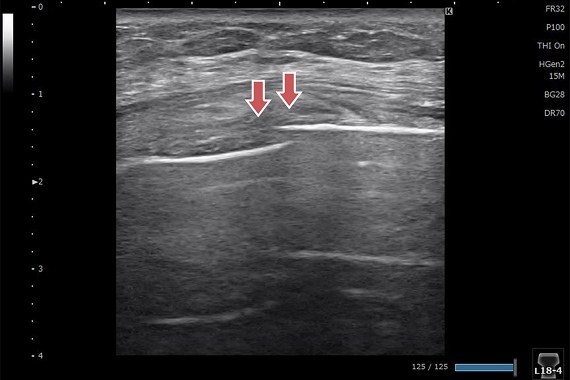

橈骨遠位端骨折

レントゲンでは分からない微小な骨折を認めます。